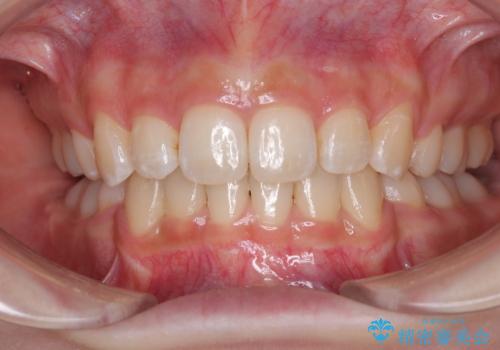

- [抜歯] ワイヤー装置で出っ歯の改善![[抜歯] ワイヤー装置で出っ歯の改善の症例 治療前](https://seimitsushinbi.jp/wp/wp-content/uploads/2025/05/IMG_1672-500x350.jpg?v=1746632084) ![[抜歯] ワイヤー装置で出っ歯の改善の症例 治療後](https://seimitsushinbi.jp/wp/wp-content/uploads/2025/05/IMG_8070-500x350.jpg?v=1746632252)

- 【モニター】舌突出癖で隙間が ワイヤー装置での抜歯矯正

- 【モニター】口が閉じられない ワイヤー装置での抜歯矯正- 担当医 藤巻太一朗

- 口が閉じられない 抜歯矯正で前歯の突出感を改善